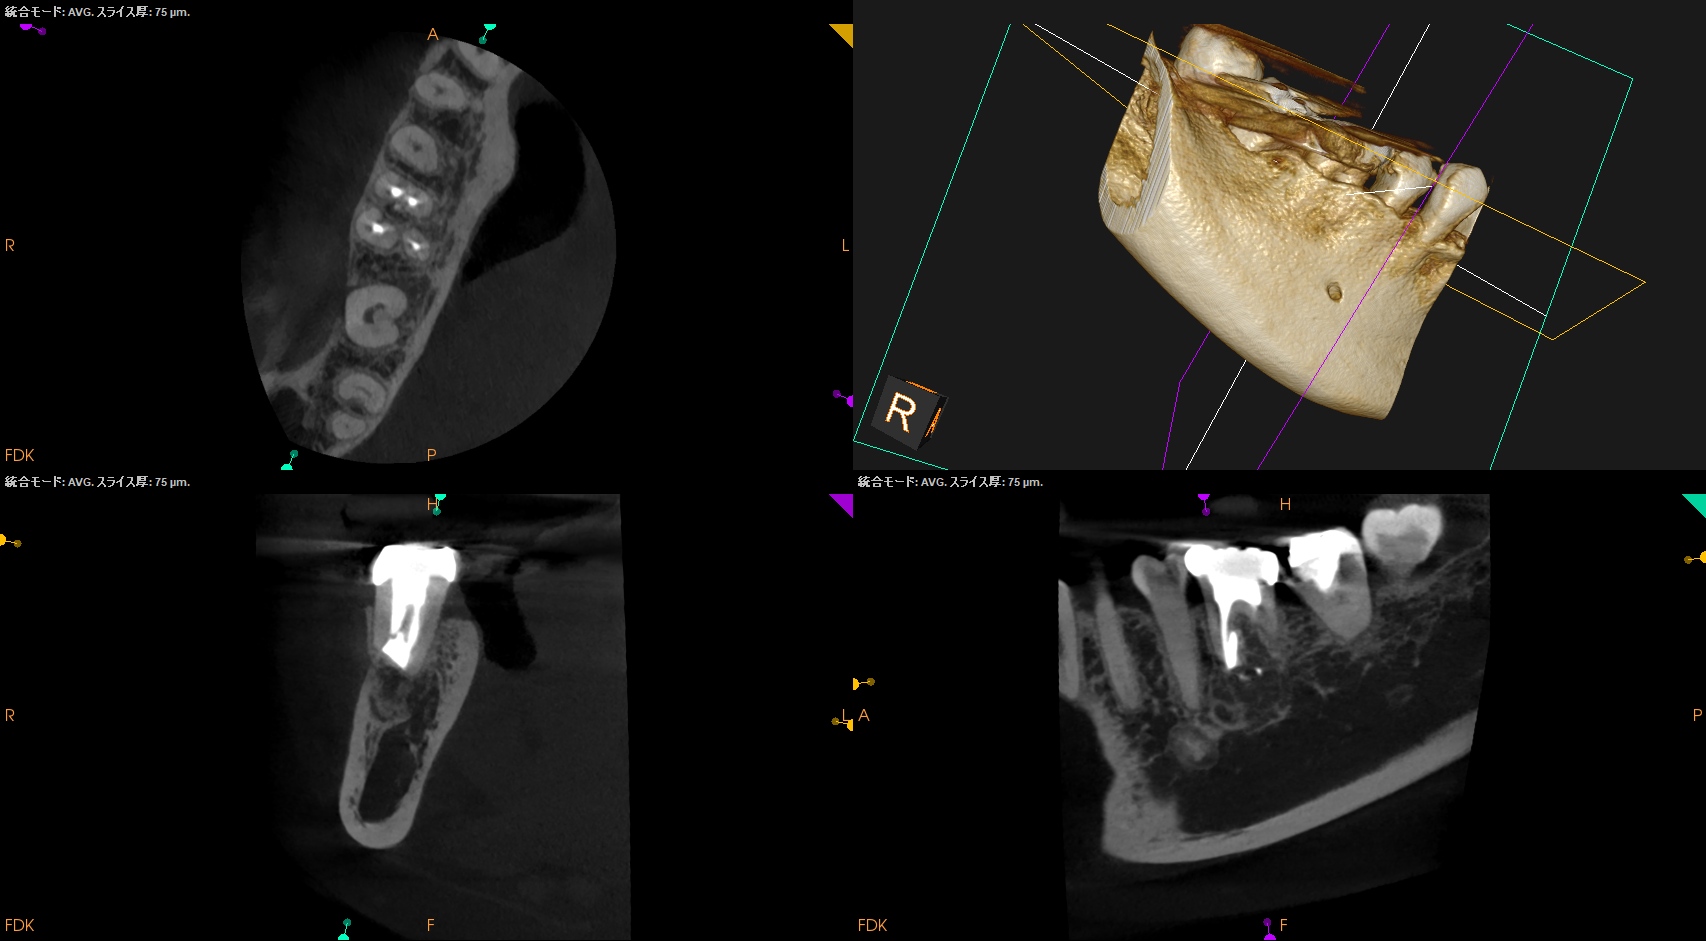

#30 M Apicoectomy 1yr recall(2025.6.23)

MB

ML

D

Radix

Apicoectomyすることで、術前の臨床症状は消失し、

D根も怪しかったが、外科をせずに治癒している。

やはり原因根はMだったのだ。

1年前の初診時と比較した。

Apicoectomyした部分は、

歯槽骨が再生した。

ということで経過観察も終診でいいだろう。